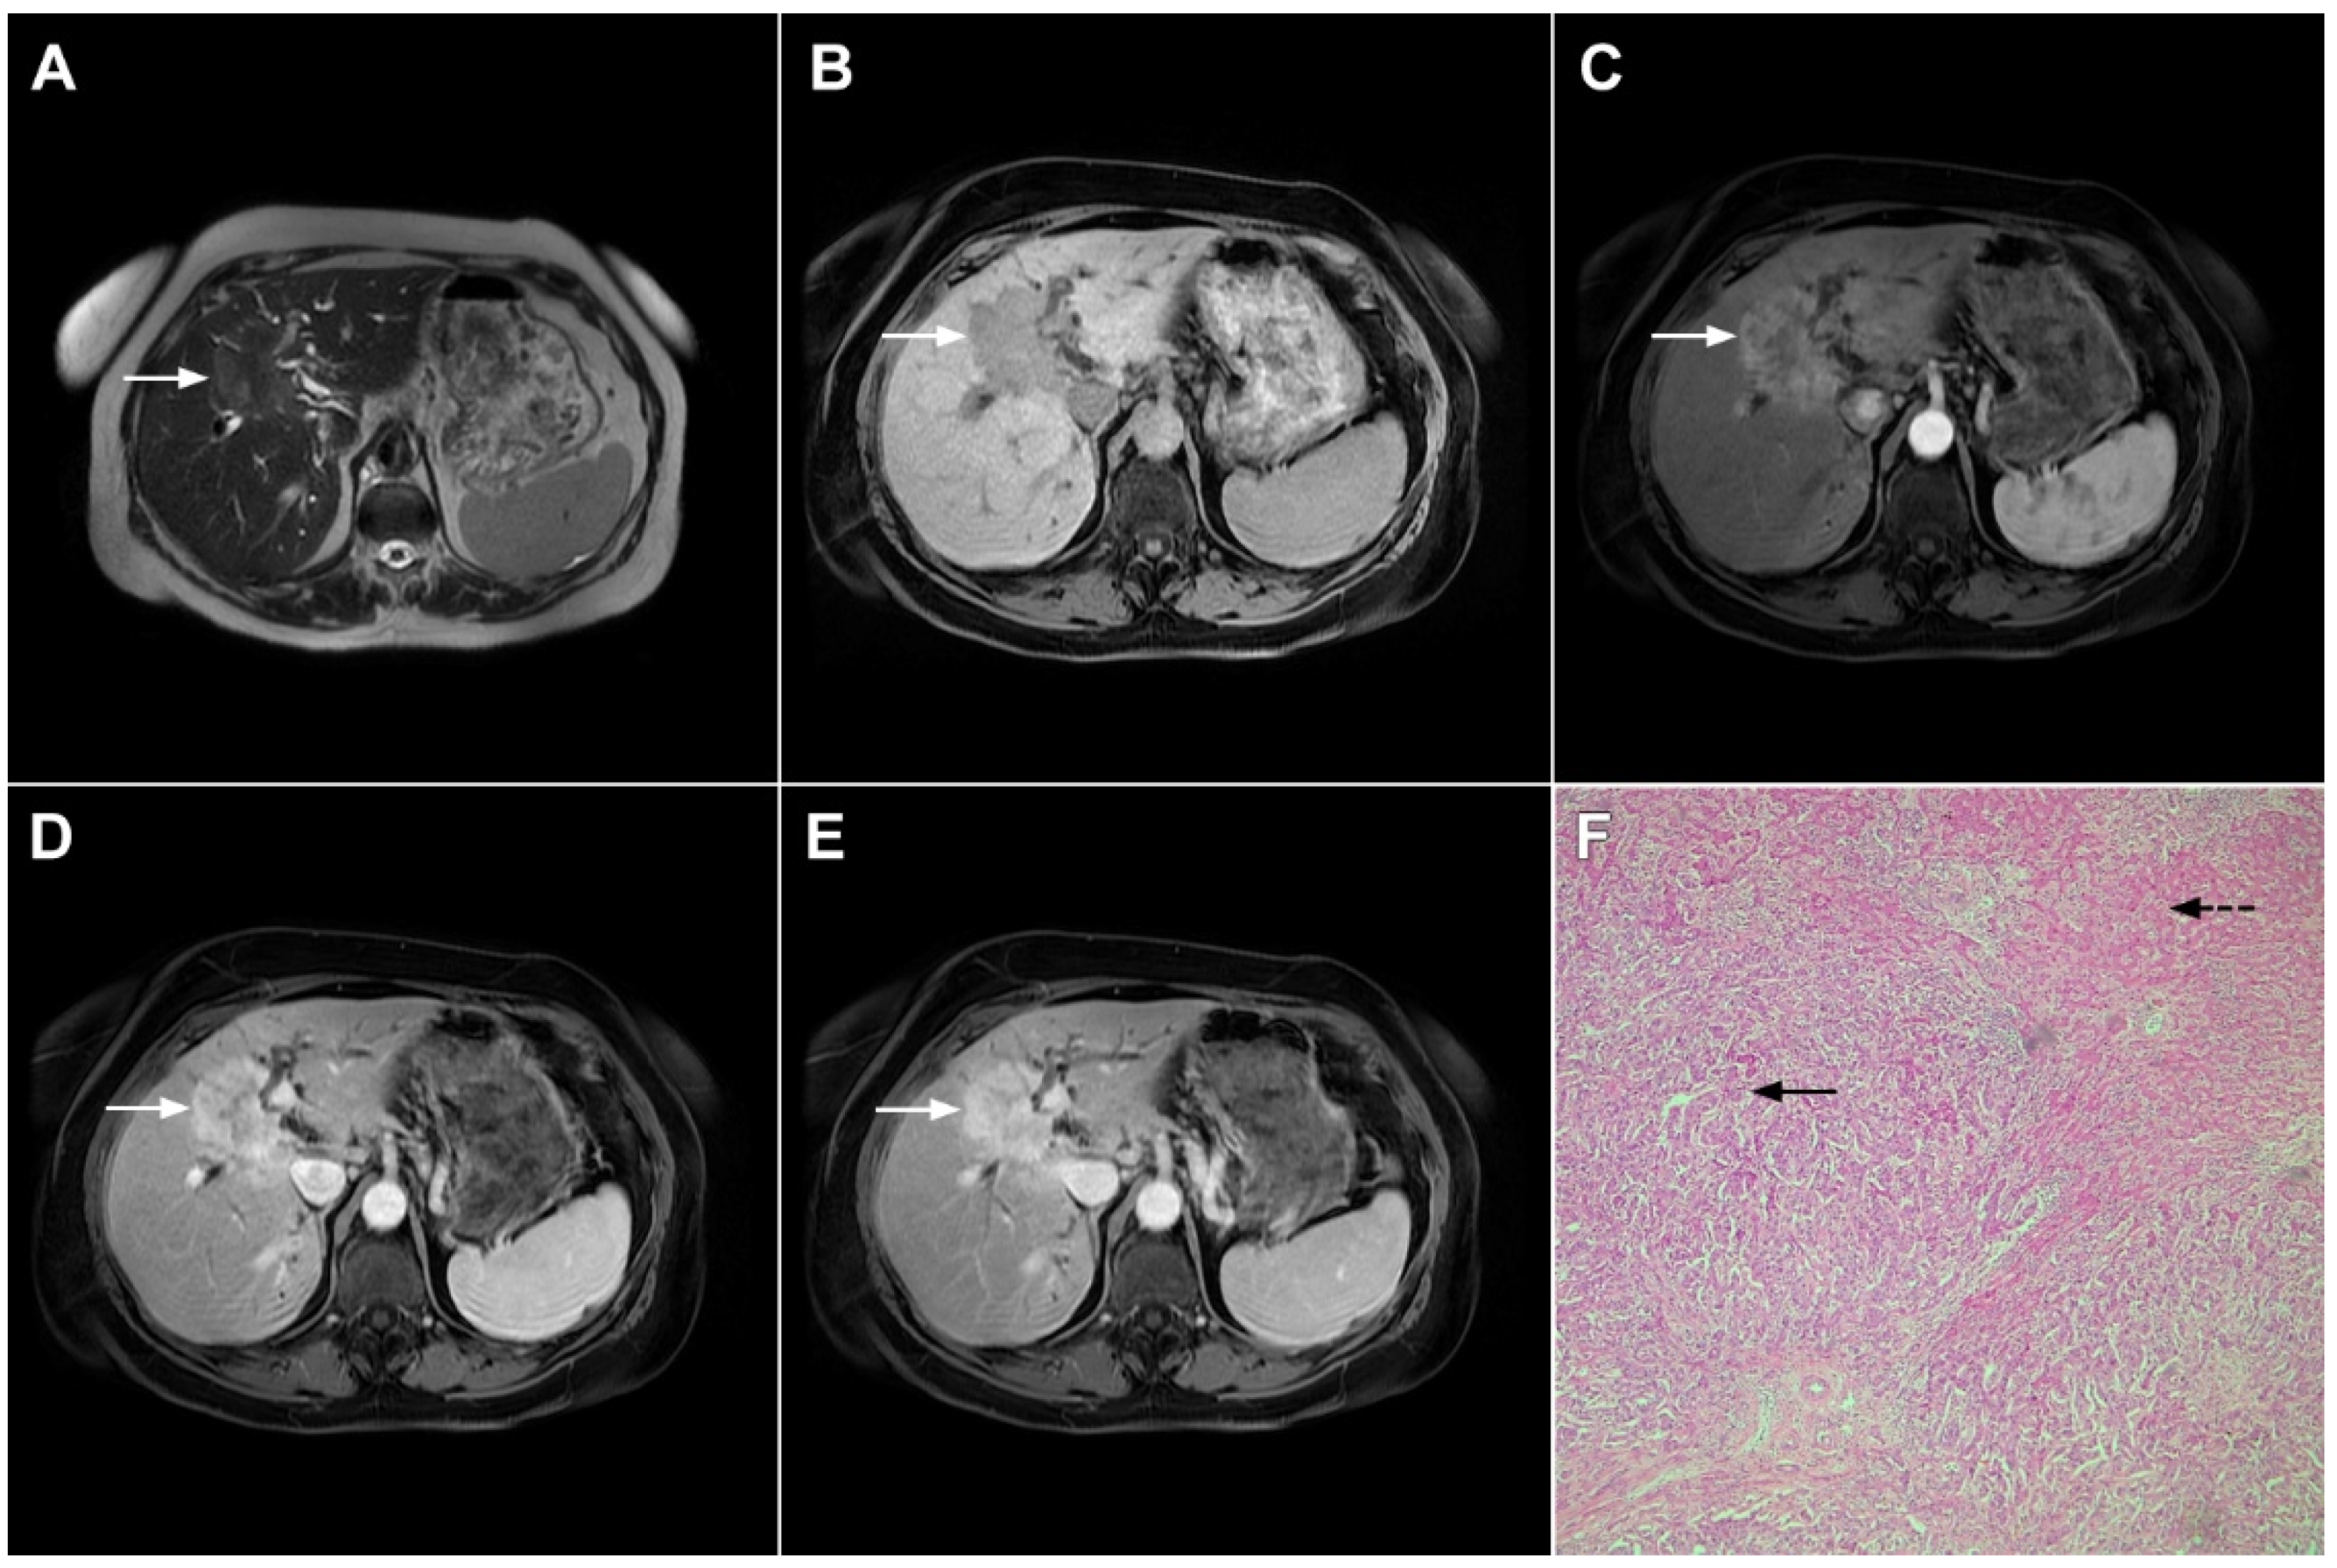

Figure 1.

Typical intrahepatic mass-forming cholangiocarcinoma in 68-year-old woman. On axial T2-weighted image a lobular heterogeneously hyperintense tumor (arrow) is seen, located centrally in the liver segment IVB (A). The lesion (arrow) is hypointense in a plain T1-weighted image (B) with irregular ring enhancements in the arterial phase (C) and progressive enhancement in the portalvenous (D) and delayed phase (E). Note the perilesional biliary dilatation. Hematoxylin and eosin (H&E) staining (F) showed cholangiocarcinoma (arrow) and normal liver parenchyma next to the tumor (dashed arrow); original magnification ×40.

However, in highly fibrotic lesions or in lesions with internal necrosis, central parts may remain non-opacified even on delayed images (Figure 2) [14].

Figure 2.

Mass-forming intrahepatic cholangiocarcinoma in 72-year-old man. Irregular heterogeneously hyperintense lesion (arrow) on T2-weighted image (A) located in liver segments IVB and III with peripheral biliary dilatation is shown. On a plain T1-weighted image (B) the lesion (arrow) is hypointense with only discrete ring enhancement in the arterial phase (C) but without detectable enhancements in the portal venous (D) and delayed phases (E). Hematoxylin and eosin (H&E) staining (F) showed poorly differentiated cholangiocarcinoma (dashed arrow); normal liver parenchyma is also shown (arrow); original magnification ×40.